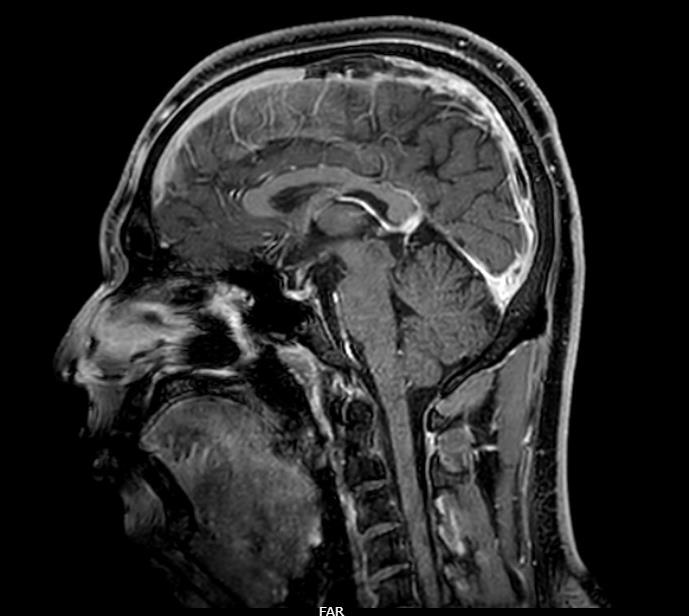

Given the history of transient left-sided weakness and suspicion of stroke, magnetic resonance imaging (MRI) of the brain was performed, which showed no acute abnormalities. In view of persistent headache with normal MRI findings, magnetic resonance venography (MRV) was obtained. MRV demonstrated a filling defect in the superior sagittal sinus, appearing hyperintense on T1-weighted images with loss of flow void on T2-weighted sequences, suggestive of cerebral venous thrombosis (CVT). The patient was subsequently shifted to the Medical Intensive Care Unit (MICU) for further management.

Figure 1:MRV (T1-weighted sequence) demonstrating a filling defect in the

superior sagittal sinus suggestive of CVT.

Transient focal deficits in CVT are uncommon and may result from transient venous congestion, regional cerebral edema, or fluctuating intracranial pressure rather than true arterial ischemia [3]. Such episodes can resemble TIA, particularly when neuroimaging does not initially reveal parenchymal lesions. In our case, MRI of the brain was normal, and the diagnosis was established only after MR venography demonstrated a filling defect in the superior sagittal sinus. This highlights the importance of venous imaging in patients with transient neurological deficits accompanied by persistent headache or other atypical features.